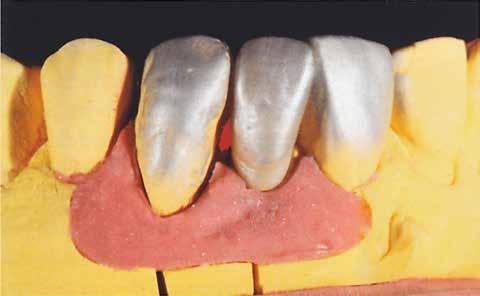

A laboratóriumban szekciós minta készült, blokk-stiftekkel (1. kép) , amelynek készítése során nagy figyelmet szenteltünk az ínymaszk (Majesthetik- Gingiimplant picodent) és a felfekvő lengőtag területének (2–6. képek)

A minta beolvasása után számítógéppel terveztük meg a híd vázát (7. kép). 0,06 mm-es cementrést terveztünk a teljes karfelület alá, 1 mmre végződve a preparáció szélétől (8–11. képek)

Így egyenlítettük ki a kötésjavító vastagságát, sikeresen. Az adatokat elküldtük az AHRtec-frézközpontba, néhány nap múlva visszakaptuk a cirkonvázat (12. kép). A marási paraméterek optimális betartása következtében a passzítás egyszerű volt (13. kép)

Az égetési hőmérséklettől függően meg kell bizonyosodnunk arról, hogy megfelelő mennyiségű anyagot hordtunk fel. A kerámiarétegzés után már nem lehet újólag felhordani Hot Bond-ot, a magas hőmérséklet miatt. A szárny felületének optikai ellenőrzése után a hídtagot kezeltük Frame-Shade-del (19. kép) . Ezután az alap -

színre színezett Liner-t hordtunk fel (20. kép) . A jobb fénytörés érdekében a Liner-t beszórtuk vállmasszával (21. kép) 16. kép 18. kép 20. kép 21. kép 17. kép 19. kép

Az égetést követően a köztes tag kialakítása volt soron. A gerinc gravírozását a kezelőorvossal történt egyeztetés szerint kell elvégezni (22. kép)

A bazális felületet vállmasszával egészítettük ki, amelyet a picodent Majesthetic Divi folyadékkal izoláltunk a mintától (23–25. képek)